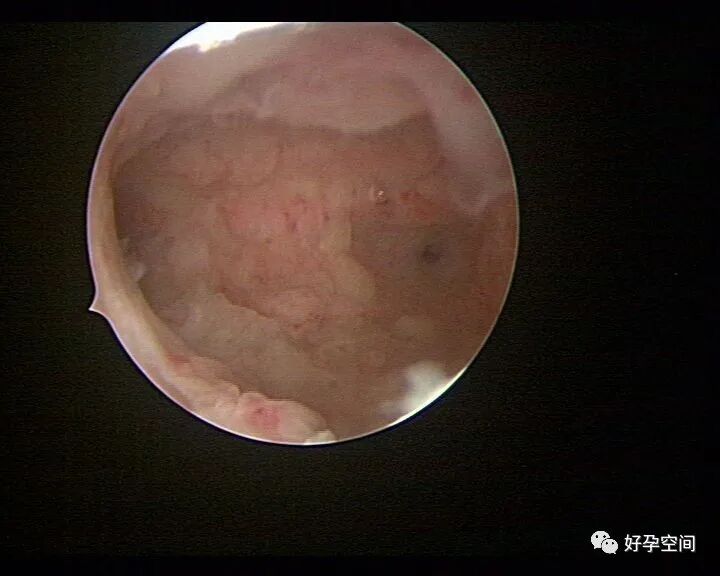

病例01:密布结节性肉芽肿